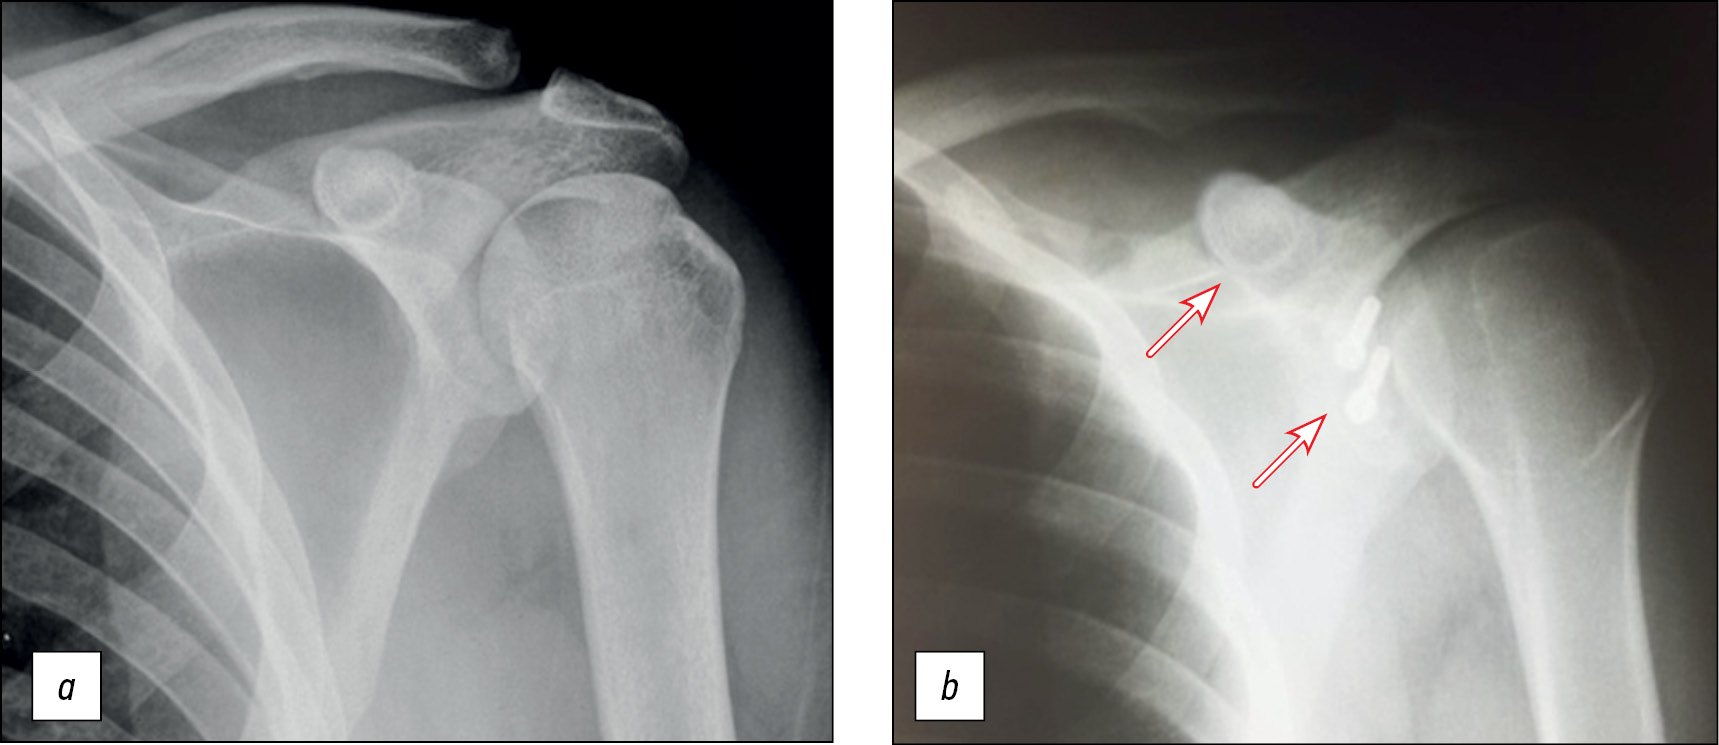

Пациент Н., 27 лет, с рецидивирующей нестабильностью левого плечевого сустава (заслуженный мастер спорта по спортивной гимнастике).

В 2022 году выполнена артроскопическая стабилизация с использованием свободного костного аутотранс-плантата правого плечевого сустава (рис. 15).

Рис. 15. Рентгенография правого плечевого сустава: а — до операции, b — через 6 месяцев после неё.

Fig. 15. X-ray of the right shoulder joint: a — before surgery, b — 6 months after it.

Положение костного аутотрансплантата через 6 мес после операции. Тестирование функционального состояния мышц через 6 месяцев после операции для оценки спектральной мощности на левой руке (рис. 16–18).